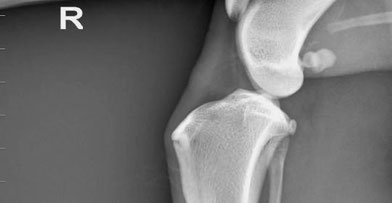

E' importante capire i segni e trattamenti di questa lesione, così come imparare a prevenirla. Il ginocchio è un'articolazione complessa formata dalla rotula, dalla cartilagine e dai legamenti che collegano il femore alla tibia. Questi componenti permettono all'articolazione di funzionare correttamente. Il ginocchio ha due legamenti stabilizzanti essenziali che si incrociano tra loro all'interno del ginocchio: il crociato craniale (o anteriore) e caudale (o posteriore). Il malfunzionamento di anche una sola parte del ginocchio può causare un elevato grado di disagio e zoppia. Dei tanti infortuni che possono verificarsi al ginocchio, la lesione del crociato è tra le più comuni.

La diagnosi viene emessa sulla base dei rilievi della visita clinica; l’esame radiografico del ginocchio può aggiungere informazioni circa la conformazione dell’arto posteriore e lo stato dell’articolazione (presenza di osteofiti, aumento liquido articolare etc.)